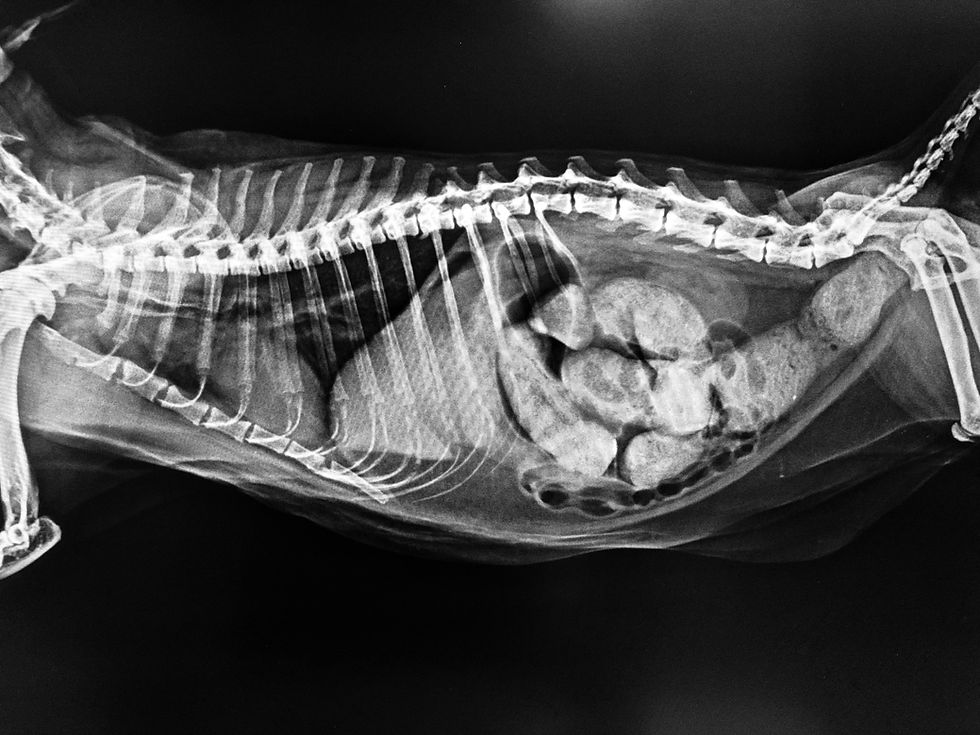

Diagnostic imaging is the cornerstone of differentiating between functional and mechanical ileus. Radiography and ultrasonography provide complementary information. Radiographs of a patient with paralytic ileus typically show a generalized and uniform gaseous or fluid distension of both the small and large intestines. This diffuse pattern is a critical distinction from the focal or segmental dilation seen proximal to a mechanical obstruction (Penninck & d’Anjou, 2015). Other radiographic findings may include a generalized decrease in serosal detail, consistent with abdominal effusion or peritonitis.

Abdominal ultrasonography provides dynamic, real-time information about intestinal motility. The key sonographic criteria for paralytic ileus are the observation of fluid-filled intestinal loops with absent or significantly decreased peristalsis (Firth, 2020). This stands in stark contrast to the non-uniform peristalsis and "pendulous movement" of ingesta often seen with a mechanical obstruction (Gaschen, 2011). The comparison of these key imaging findings is fundamental to clinical decision-making.

Radiography | Generalized, uniform gaseous distension of the large and small intestines | Focal or segmental dilation of intestinal loops proximal to the obstruction site |

Ultrasonography | Fluid-filled loops with absent or decreased peristaltic activity | Non-uniform peristalsis and pendulous movement of ingesta |